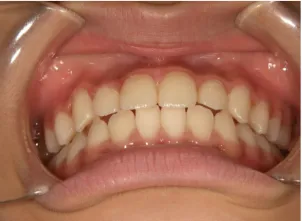

治療後⑩高2:17y7m 抜歯治療終了

口元の治療前後:15y5m→17y7m スッキリしました

| 行ったご提案・診断内容 | 成長期に行う治療と咬合治療をご提案 咬合治療でOPEにならないように、成長期に受け口の悪化予防を行い、咬合治療で歯並びと口元の改善を行うことを提案しました。 《成長期治療:成長時期にお口の環境を整え、適正な成長を誘導する治療》 使用装置 《咬合治療:成長期治療後に大人の歯を咬ませる治療》 *治療は上記ステップで行いました。 《治療後の経過観察》 |